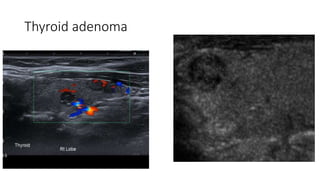

Thyroid adenoma